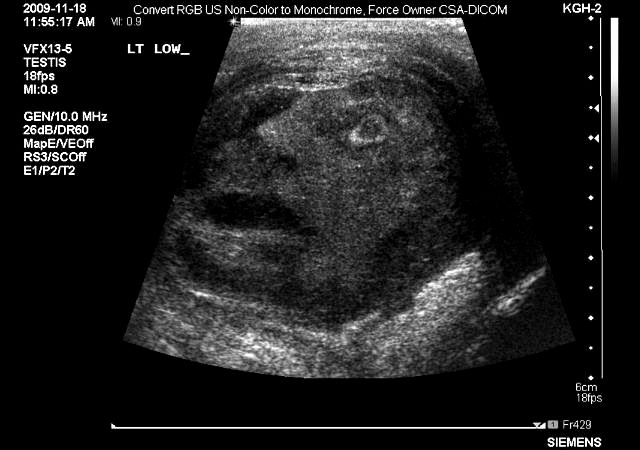

G. Gregori Roberts i Nadži J. Tuma, sa Kivins univerziteta u Ontariju izvršili su pregeled ultrazvukom kako bi proučili neobičnu masu u testisu jednog 45-godišnjeg pacijenta koji se žalio na jake bolove.

Ugledali su zapanjujuću sliku i proslijedili je časopisu "Urology". Ne samo da je postala slika mjeseca, već je ubrzo preplavila internet poput virusa.

„Doktori i drugo osoblje bili su zapanjeni kad su ugledali konture muškog lica kako zuri u posmatrače, sa razjapljenim ustima, kao da je i samo proživljavalo ozbiljan epididimo-orhitis”, pisalo je u propratnom tekstu uz sliku.

"Uslijedila je kratka debata da li je ova pojava znak nekog božanstva (možda Mina, egipatskog boga muške plodnosti?), međutim, konsenzusom smo zaključili da je prije riječ o slučajnosti nego o božanskom javljanju“.

Pacijentu je uklonjen testis a ispostavilo se da je masa bila benigna.